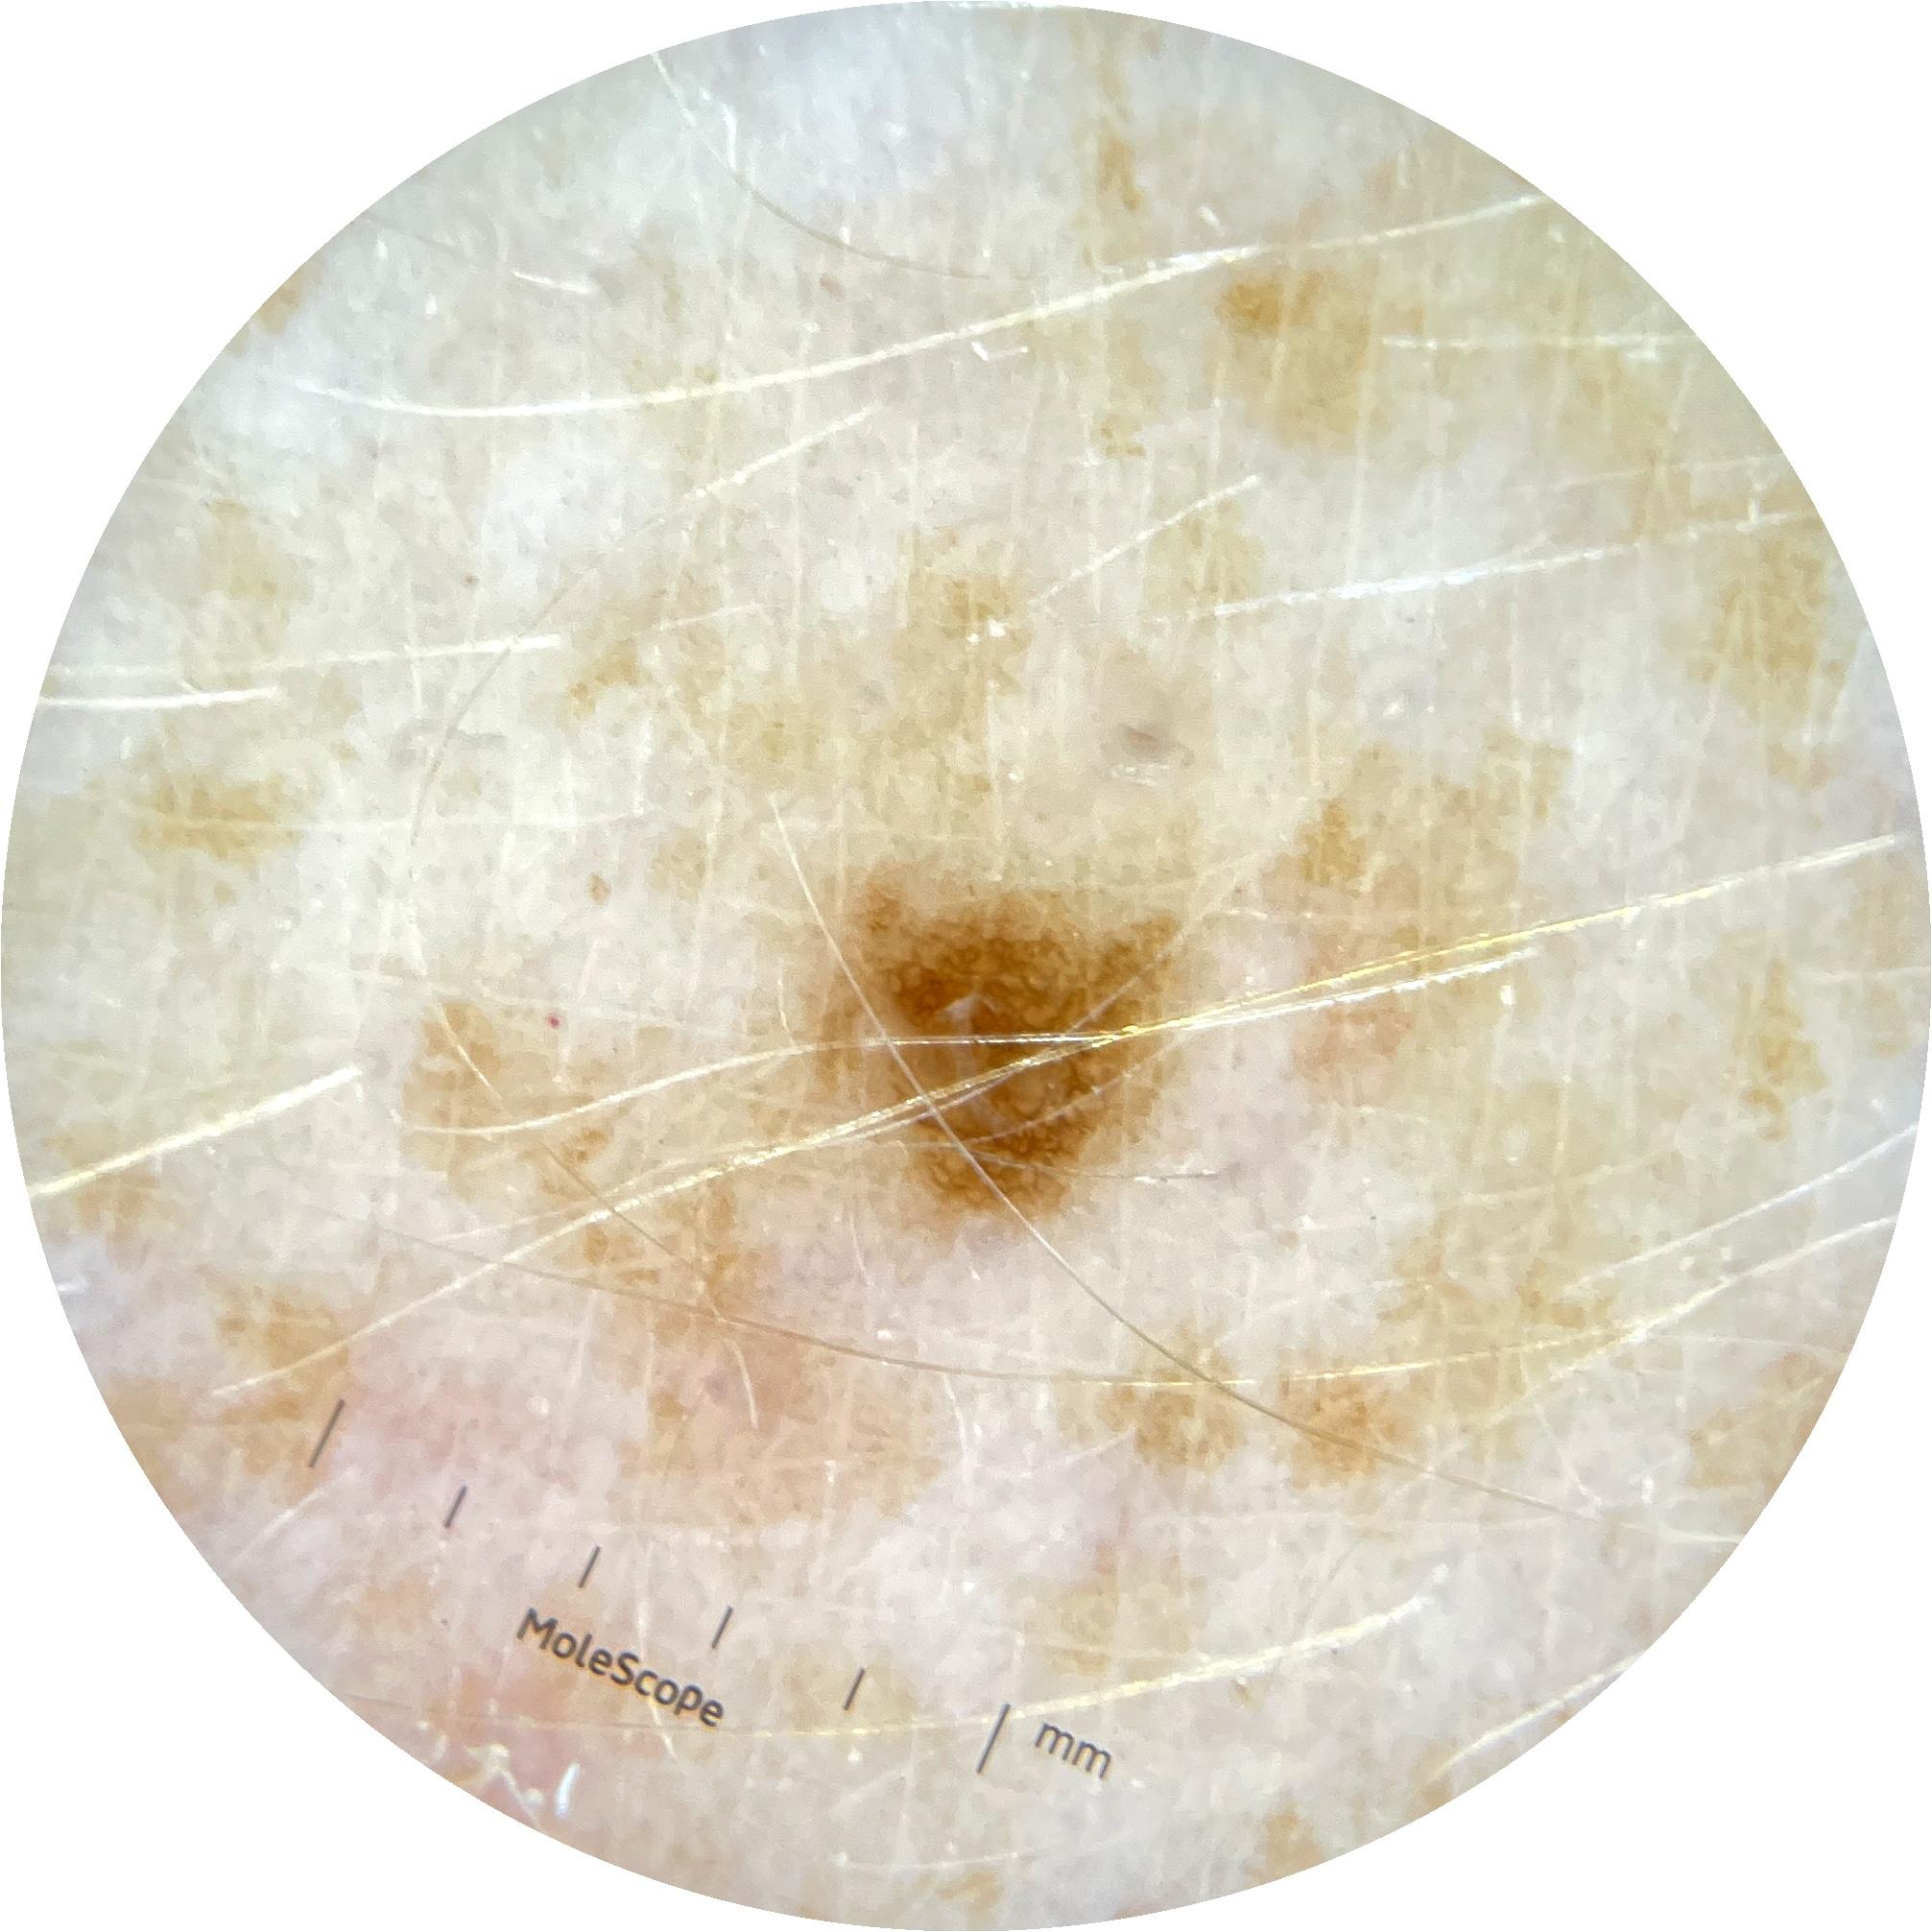

ISIC_9785574

Clinical

Field Value

acquisition_day 148

age_approx 45

anatom_site_1 Head and neck

anatom_site_general head/neck

concomitant_biopsy False

diagnosis_1 Benign

diagnosis_confirm_type single image expert consensus

family_hx_mm True

image_manipulation instrument only

image_type dermoscopic

lesion_id IL_0236417

patient_id IP_8456088

personal_hx_mm True

sex female